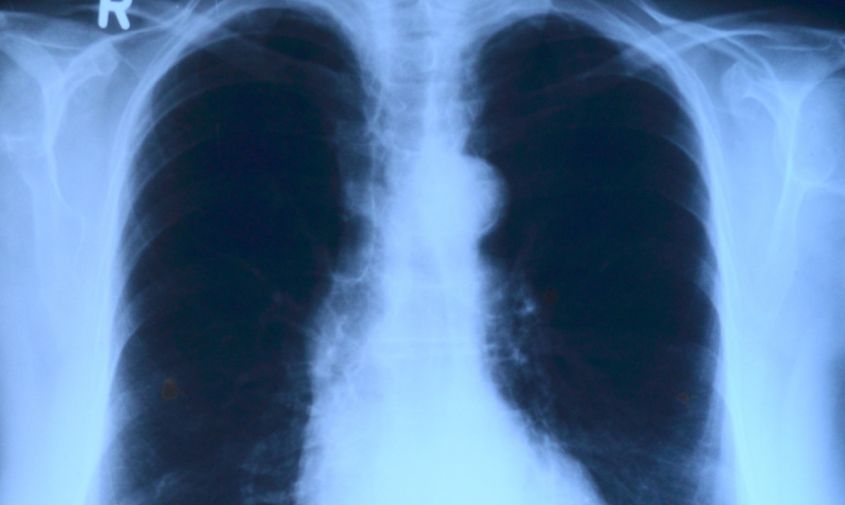

В Приамурье немного снизилась заболеваемость ОРВИ, но продолжает расти количество выявленных пневмоний. Об эпидемиологической обстановке в регионе за прошлую неделю рассказали в амурском управлении Роспотребнадзора.

Продолжается рост заболеваемости внебольничными пневмониями. На прошлой неделе зарегистрировано 288 случаев, в том числе 161 среди детей, что на 25 % выше уровня предыдущей недели.